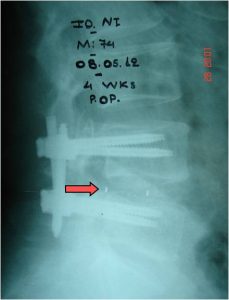

- α

- β

- γ

Εικόνα 10 (α,β,γ) : Προσθιοπισθία (α) και πλαγία (β) μετεγχειρητική ακτινογραφία. Ο μεσοσπονδύλιος δίσκος Ο4-Ο5 έχει υποκατασταθεί με ακτινοδιαπερατό μεσοσπονδύλιο εμφύτευμα που τοποθετήθηκε διαδερμικά, επιπλέον δε έχει γίνει διαδερμικά η σπονδυλοδεσία. Στη φωτογραφία (γ) φαίνονται οι χειρουργικές τομές στο δέρμα που έχουν μήκος περίπου 2 ½ εκατοστά.